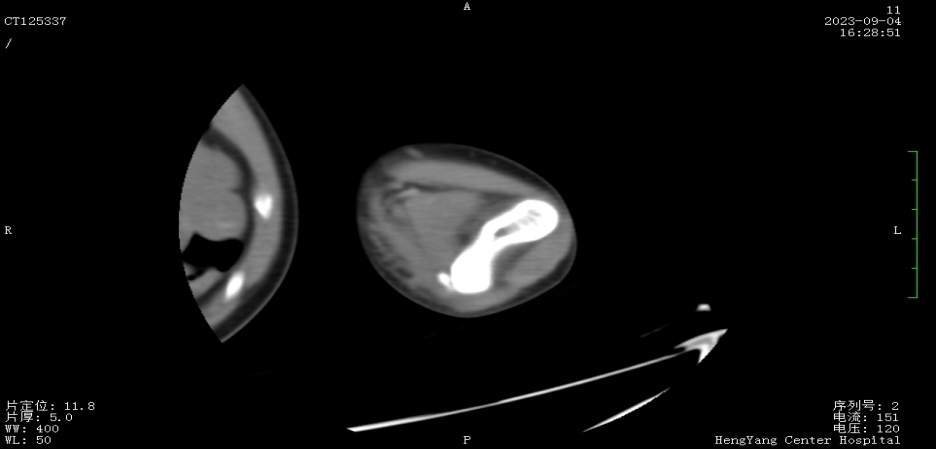

接診后,醫(yī)師發(fā)現(xiàn)小莫同學(xué)的左肘關(guān)節(jié)自然狀態(tài)下僅能伸展至約115°,并伴有習(xí)慣性屈肘。經(jīng)與骨科醫(yī)生溝通并閱片后,考慮骨化肌炎,針對(duì)這種情況,一般采取手法松解關(guān)節(jié)和關(guān)節(jié)功能鍛煉相結(jié)合的治療方案。但此方案常用于成人患者的關(guān)節(jié)粘連傳統(tǒng)松解術(shù)和關(guān)節(jié)松動(dòng)訓(xùn)練,對(duì)于兒童來(lái)說(shuō)刺激強(qiáng)度太大,且因兒童骨骼及關(guān)節(jié)較成人脆弱,無(wú)法保證治療的連續(xù)性及安全性,若一味采取輕柔手法,不僅治療時(shí)間長(zhǎng)、見(jiàn)效慢,還可能加重后續(xù)治療難度